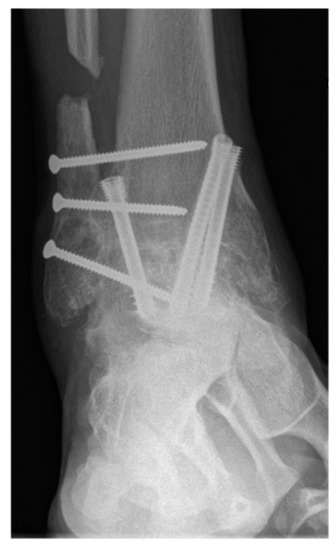

Figure 4.

A 62-year-old female patient presenting complete union of the tibiotar and distal tibiofibular joints at 4 months follow-up.

The primary outcome measure was nonunion rate of tibiotalar arthrodesis [2]. Union was defined based on patient reported symptoms and clinical physical examination criteria (no pain, no warmth, improvement in swelling, and stability to stress) and radiographic criteria (visible trabecular bridging across the arthrodesis site and no lucency around the hardware) [40]. Appropriate osseous union was defined as trabecular bridging across the tibiotalar joint (at least 80%) within 6 postoperative months [41] (Figure 3 and Figure 4). In patients with nonunion, computerized tomography (CT) was utilized for further assessment and was evaluated by independent radiologist not involved in any of surgeries. Secondary outcome measures were wound complications, return to the operating room, and rate of development of post-operative deep vein thrombosis (DVT), or pulmonary embolism (PE).